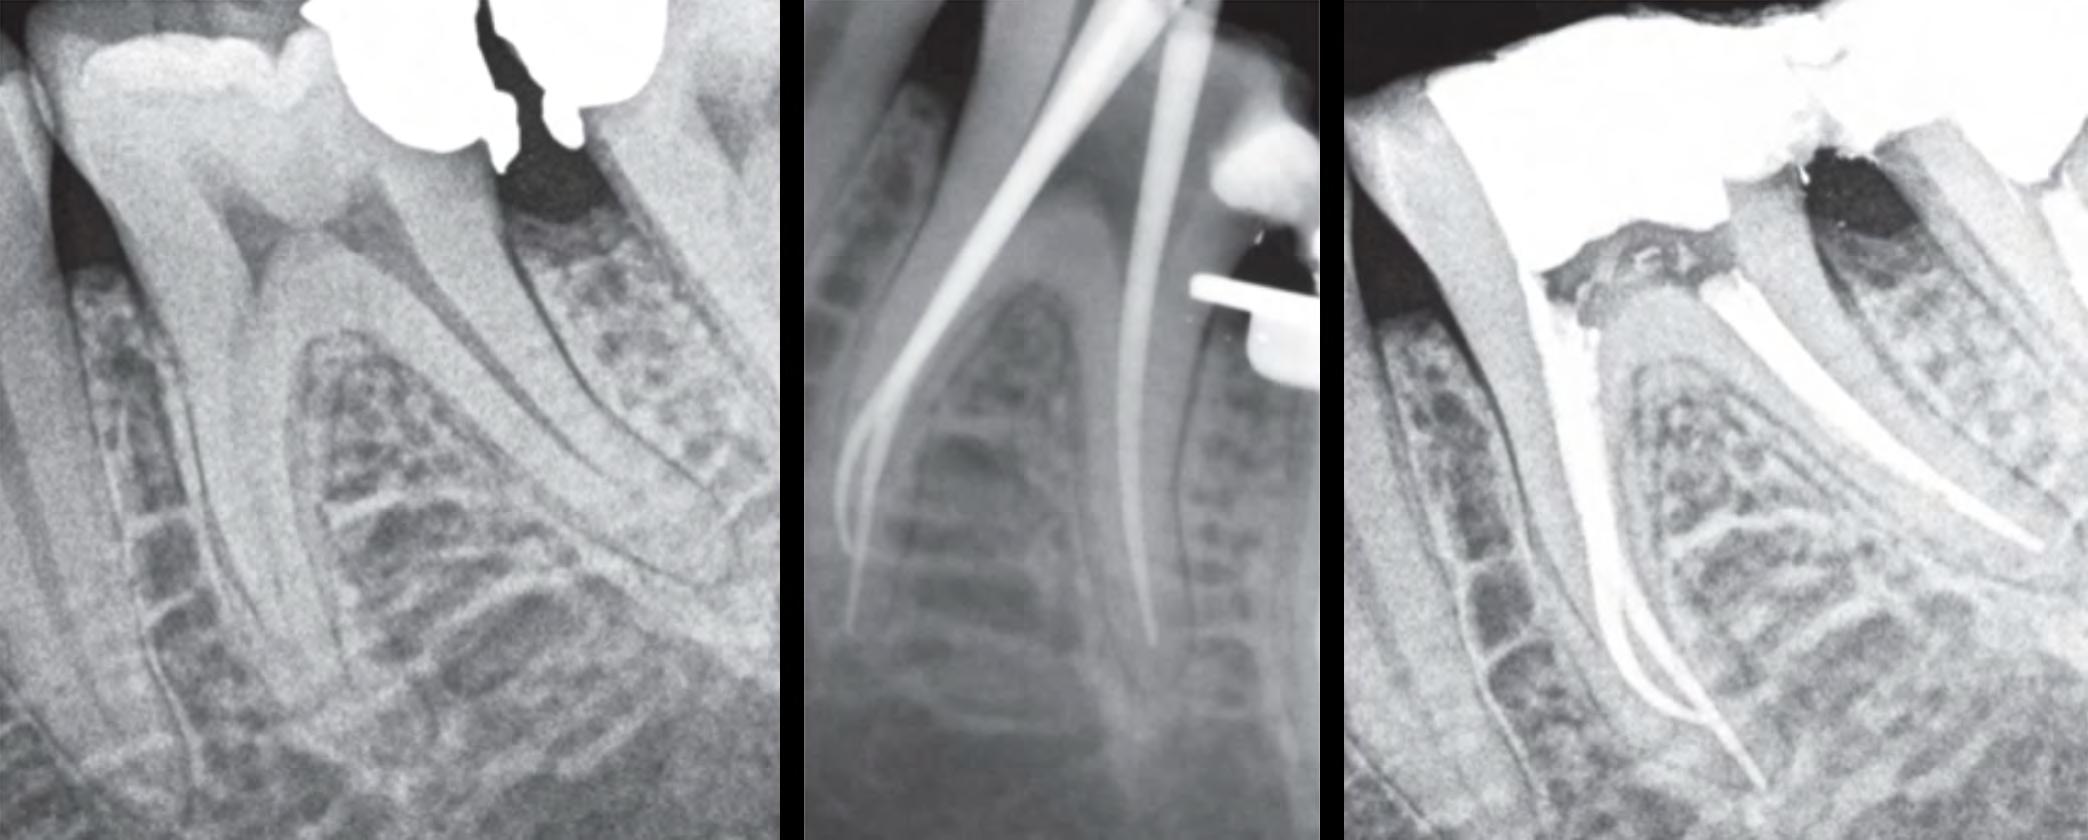

The patient was referred to our endodontic practice for evaluation and treatment of tooth 36. Clinically #36 had MOD composite restoration, a negative response to cold, and tenderness to percussion. Pre-op x-ray revealed #36 had a small periapical radiolucency associated with the Mesial root and a moderate size associated with the Distal root. Pulpal Necrosis with Symptomatic Apical Periodontitis. Endodontic diagnosis: Tooth #36 was accessed, located MB, ML, and DB and DL canals. Canals instrumented with EdgeFile X7 rotary files using a crown down technique. Pre-Op – James A. Wealleans, D.M.D, American Board Certified Endodontist, Adj Professor, Clinician Sydney, Australia

Working lengths were determined via apex locator followed by radiographic confirmation. The canal system was obturated with bioceramic sealer (BUSA, BC Sealer). The access was immediately restored with a fiber reinforced dual cure core material. Sequence of files for ‘crowndown’ (with MAF sizes) X7s 25.06 to resistance, then 20.06 to resistance, then 25.06 to resistance. Working length hand file to 15, 17.04 if necessary, 30.04, 35.04, 40.04. For this case, my final rotary file was a 40.04 at 500 RPM and 2.6 N/cm torque. Post Obturation Final